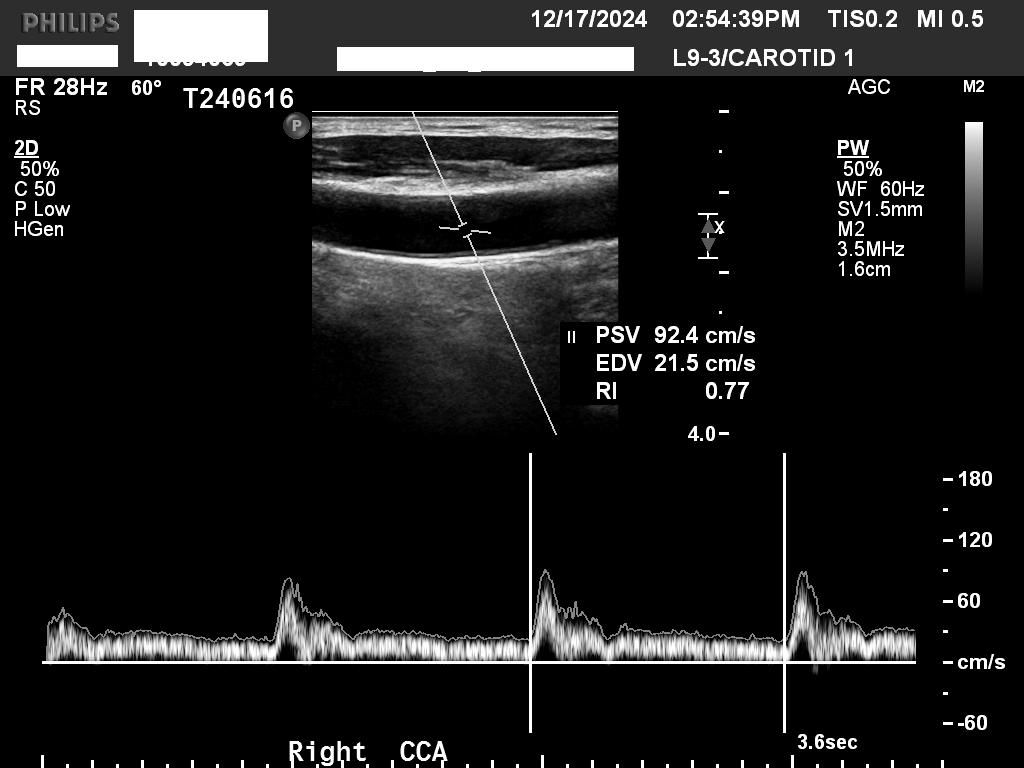

2024년 지난해말 처음으로 경동맥 초음파검사 했는데, 어느정도 수준일까요?

• 1번 째 사진

일반적으로 IMT가 1mm 보다 두꺼운지를 확인하고 혈관에 플라크가 있는지를 봅니다

초음파 사진으로만 보면 동맥경화가 경증으로 있는 것 같습니다